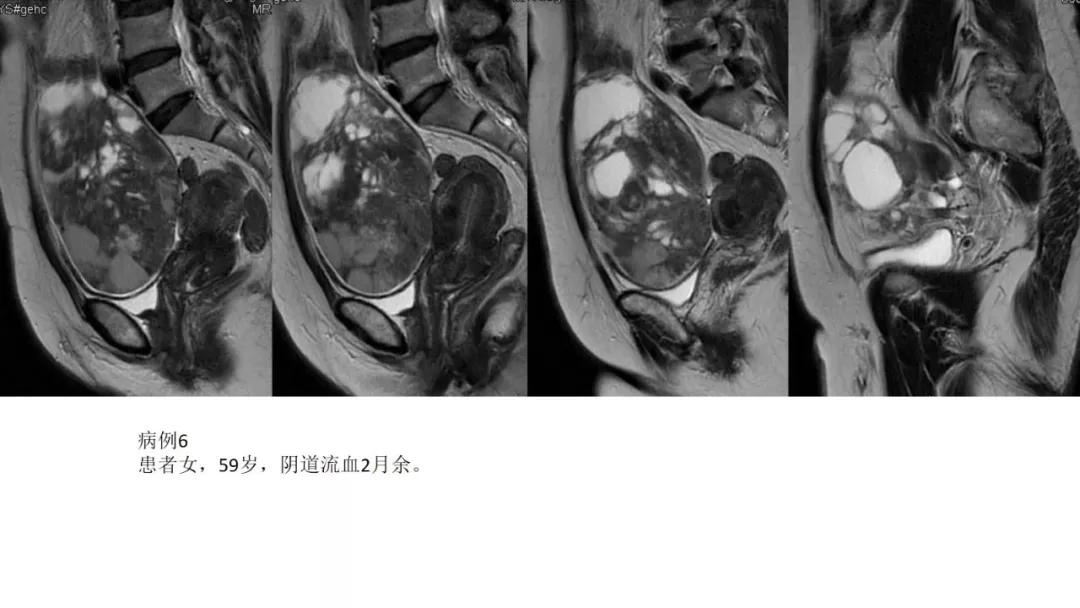

病理:浆液性囊腺癌

病理:颗粒细胞瘤

病理:子宫肌瘤粘液样变性